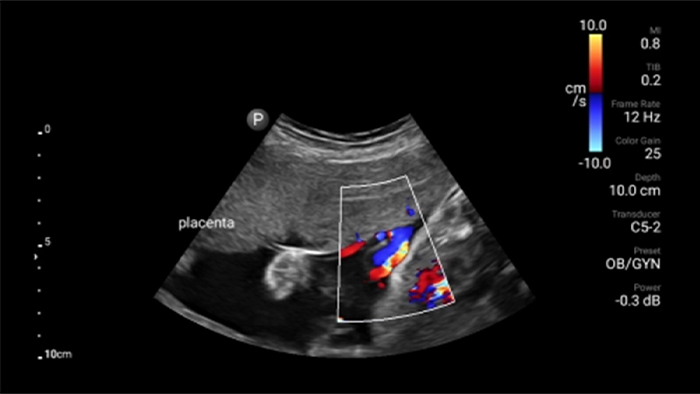

Focused renal ultrasound